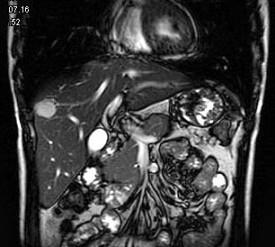

问题 男,42岁。体检B超发现肝内占位,行MRI检查见肝右叶长T1长T2异常信号。依据MRI图应诊断为 ( )

选项 A、肝脏单发转移瘤 B、未见异常 C、肝血管瘤 D、肝癌 E、肝囊肿

答案 C